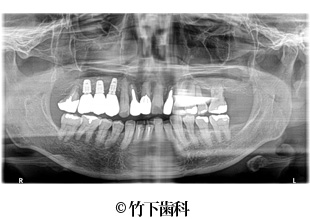

【症例2】右下臼歯部3本欠損のインプラントによる治療

- 治療前

- 治療後

- 治療名

- 右下臼歯部3本欠損のインプラントによる治療

- 費用

- 605,000円(税込)

【内訳】

インプラント埋入術

220,000円(税込) × 2

インプラント上部構造

55,000円(税込) × 3

- 期間

- 5ヵ月

- 通院回数

- 11回

- 患者様

- 50代女性

治療内容

-

患者様の症状

部分入れ歯を長年使用していて、奥歯で噛むことに困難を感じていました。食べ応えのあるものをしっかりと噛みたいというご希望がありました。

治療法

下顎の欠損部分に2本の人工の歯根を埋入しました。そこに3本の歯の形をしたブリッジの上部構造を装着しました。

治療結果

インプラント埋入術によって人工歯根を形成し、その上に上部構造を作ったことで、ご本人の歯のように安定して食べものを噛めるようになりました。2本のインプラントにブリッジの上部構造を装着することで、3本の歯があるような見た目になりました。

そのほか

患者様のご希望を聞いて、天然歯はなるべく残すような治療をしています。

※治療結果は患者様によって個人差があります。

治療を行う上での 注意点 (リスク・副作用)

出血、腫脹、疼痛、神経麻痺、補綴物のダツリ、破折、インプラント体の破折、咬合違和感、インプラント周囲炎